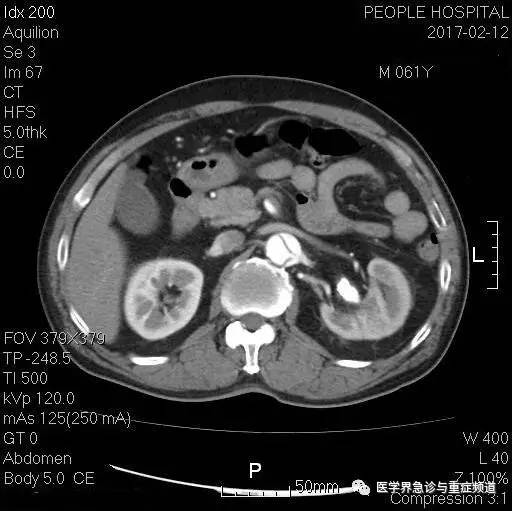

正思索这病例会不会是肾绞痛,猛然看到一个让人一惊的CT征象-钙化斑内移,赶紧增强确认。

增强CT可见主动脉内真假腔形成,典型的主动脉夹层,左肾动脉开口于假腔,稍缺血,可能因此出现肾区叩击痛和类似肾绞痛,肠系膜上动脉也有受累。

平扫CT上看到的那点腹主动脉内钙化斑内移正是提示此处内膜存在撕裂的征象。